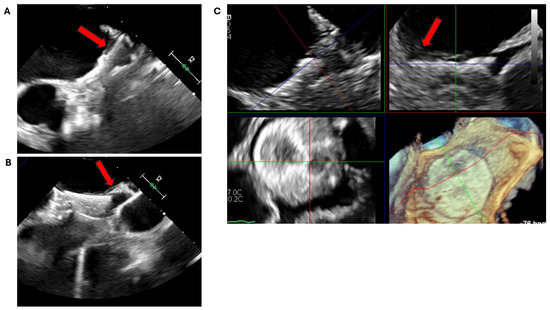

3.1. Device Position and Embolization

3.2. Peri-Device Leaks

3.3. Device-Related Thrombus

3.4. Pericardial Effusion and Device Erosion